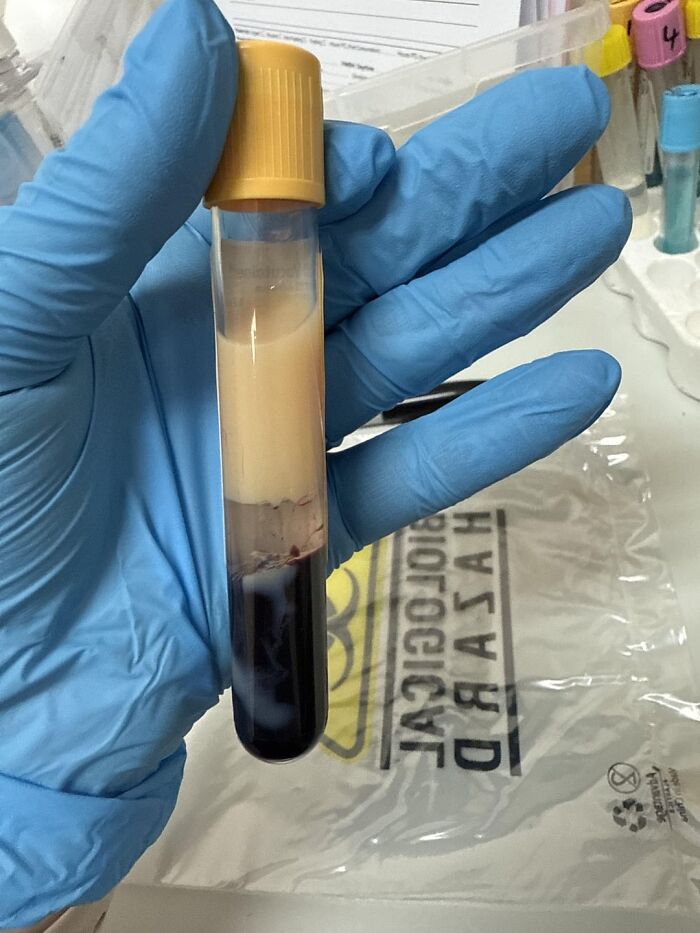

Blood Collected From A 34 Yo Man Today